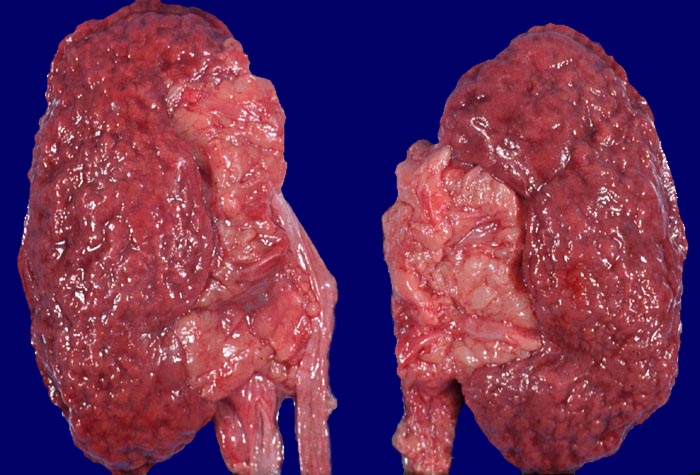

Morphologie der PAN:

In den beteiligten Organen sind nicht alle Arterien pathologisch verändert und oft ist die Gefässwand nicht zirkulär sondern nur segmental betroffen und die Gefässveränderungen befinden sich in unterschiedlichen Stadien. Folgen der Gefässveränderungen sind Infarkte und Mikroaneurysmata. Die Nieren sind im akuten Stadium oft vergrössert. An der Oberfläche sind Petechien neben unterschiedlich grossen Infarkten erkennbar. Gelegentlich erkennt man auf der Schnittfläche Gefässaneurysmata, thrombosierte Arterien und Papillennekrosen. Im häufigeren chronischen Stadium sind die Nieren verkleinert und aufgrund von Infarktnarben grob gebuckelt. Befallen sind prärenale und grössere intrarenale Nierenarterienäste bei meist fehlender Beteiligung der Arteriolen und definitionsgemäss fehlendem Befall der glomerulären Kapillaren. Die betroffenen Gefässe zeigen segmentale transmurale oft durch Thrombosierung komplizierte Wandnekrosen mit initial granulozytenreichem Infiltrat. Im Verlauf werden die Nekrosen durch Granulations- und Narbengewebe organisiert. An grossen Arterien kann dies zu Knotenbildungen und Aneurysmata führen. Oft findet man in ein und demselben Gefäss frische Nekrosen neben reparativen Veränderungen und Narben. Das übrige Nierengewebe zeigt als Folge der Vaskulitis Kollapsglomerula, Infarkte und ischämische Tubulusatrophie mit begleitender interstitieller Fibrose und Entzündung.